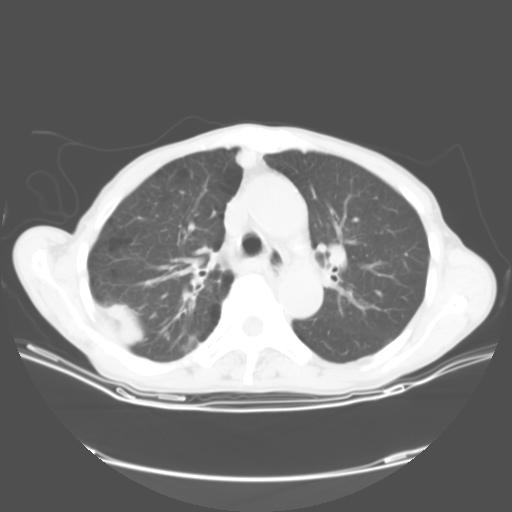

女,72岁,咳嗽一周余,突发右下肢无力二天。

pe:bp-140、80mmhg,精神可,伸舌居中,右上肢肌力正常,右下肢肌力0级,巴氏征+

来院做头颅+胸部ct平扫

遂加作增强:

胸部病变平扫35hu,增强强化至70hu

这个病人首先是胸部病变的定位到底是肺内还是肺外。仔细观察块影位于胸膜下,与胸膜间有透亮带,且近端血管未见明显推移而是引流样改变,形态分叶,说明这个病灶位于肺内胸膜下。很可能是腺癌,腺癌最易致颅内高密度转移灶。局部胸膜有侵犯。

本例颅内见多发大小不等高密度灶,有强化及水肿;另外,胸锁关节层面可能是第四胸椎及右侧肋骨起始部骨质欠连续,椎旁软组织肿胀,建议调骨窗观察。

诊断:右下肺癌伴颅内、胸椎、肋骨转移可能性最大。